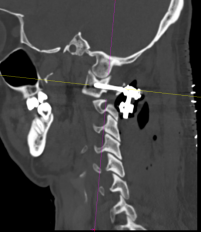

该患者的治疗关键在于两个方面:一是能否将螺钉置入漂浮的寰椎侧块中从而达到骨折的复位及固定?二是该患者同时还伴有双侧枢椎椎弓根先天性发育不良、椎动脉高跨,能否顺利植入椎弓根螺钉?经过为期一周的颅骨牵引和术前准备,杨先生于近日接受了手术。对于此类颈椎手术,经验丰富的姜为民主任早已开展了多年,与以往不同的是这次手术多了一台“GPS”---“O”-臂机,这也是我院首次术中开机实用。

术中“O”-臂机导航图像

在麻醉手术科的配合下,有了高精尖的第二代“O”-臂机的辅助,加之姜主任丰富的临床经验,手术非常顺利。第二代“O”-臂机扫描颈椎三维重建显示寰椎移位的骨块复位完成,寰枢椎椎弓根螺钉位置良好。术后,患者颈部疼痛症状明显改善。